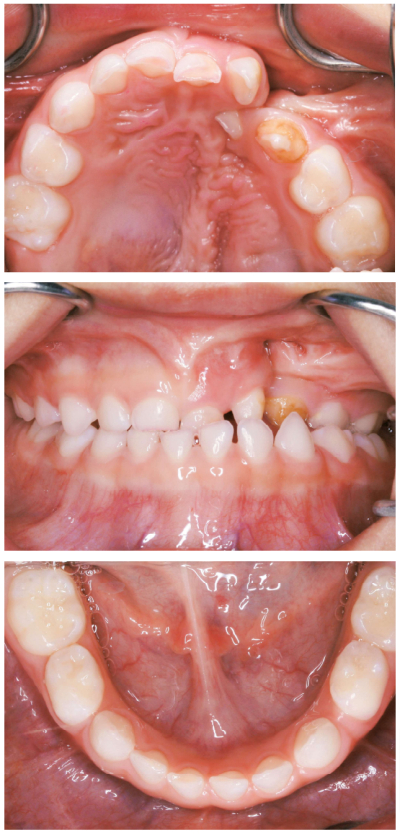

4歳の男児。定期的な口腔管理を希望して来院した。生後3か月時に口唇閉鎖術、1歳2か月時に口蓋形成術を受けたという。来院時の顔貌写真と口腔内写真を別に示す。現時点で行うべき対応はどれか。2つ選べ。

a. 食事指導

b. 過剰歯の抜去

c. 口腔衛生指導

d. 上唇小帯切除術

e. 上顎左側乳中切歯の抜去